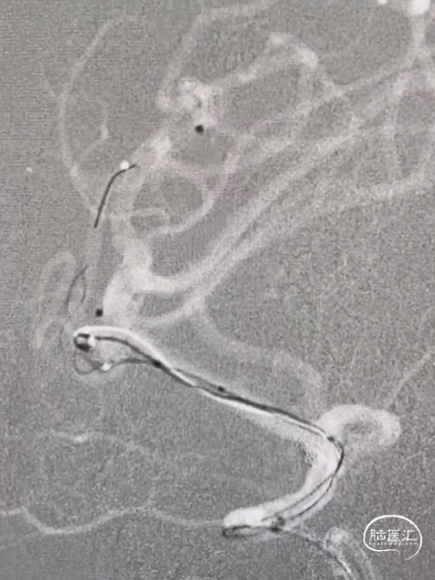

因下干支与M1成角太锐,支架在转弯处打开,多次推拉调整,以“神龙摆尾”方式释放,将支架尾端避开上干开口。

释放支架后,再依次送入2*3mm、1.5*2mm两枚弹簧圈完成治疗。

术后造影显示各分支血管通畅,动脉瘤不再显影。